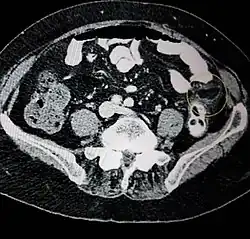

Peritoneal loose body

Gross pathology of a peritoneal loose body, caused torsion and autoamputation of an epiploic appendage, which eventually becomes embedded in a fibrous capsule.

It is rare however possible for epiploic appendagitis to result in a peritoneal loose body. Peritoneal loose body is a free floating mass of dead fibrous tissue surrounded by several layers of calcification (deposit of calcium salts). The loose body is the result of torsed, infarcted or detached epiploic appendages that eventually become fibrotic (inflammation and scarring) masses. If the loose body becomes large enough it can cause urinary retention (inability to empty bladder) or bowel obstructions.[3]